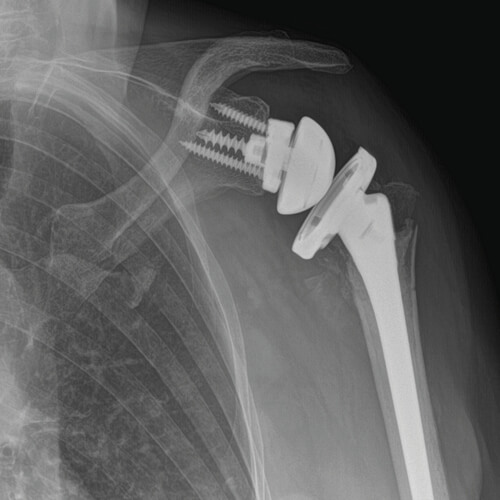

L’importanza della protesi di spalla navigata

La protesi tramite navigatore GPS è una delle tecniche più all’avanguardia e più efficaci nel trattamento dell’artrosi. Con l’uso di un software specifico, a partire da una TAC, è possibile ricostruire la spalla in 3D e pianificare le dimensioni e il posizionamento delle componenti protesiche. Durante la procedura chirurgica, le mani del chirurgo sono guidate da uno strumentario dedicato legato a dei sensori, così da permettere l’impianto della protesi nell’esatta posizione pianificata al computer, con un ordine di errore infinitesimale.

I vantaggi della protesi tramite navigazione GPS:

- maggiore precisione nel posizionamento dell’impianto,

- meno rischio di complicanze intraoperatorie,

- maggiore sopravvivenza dell’impianto.